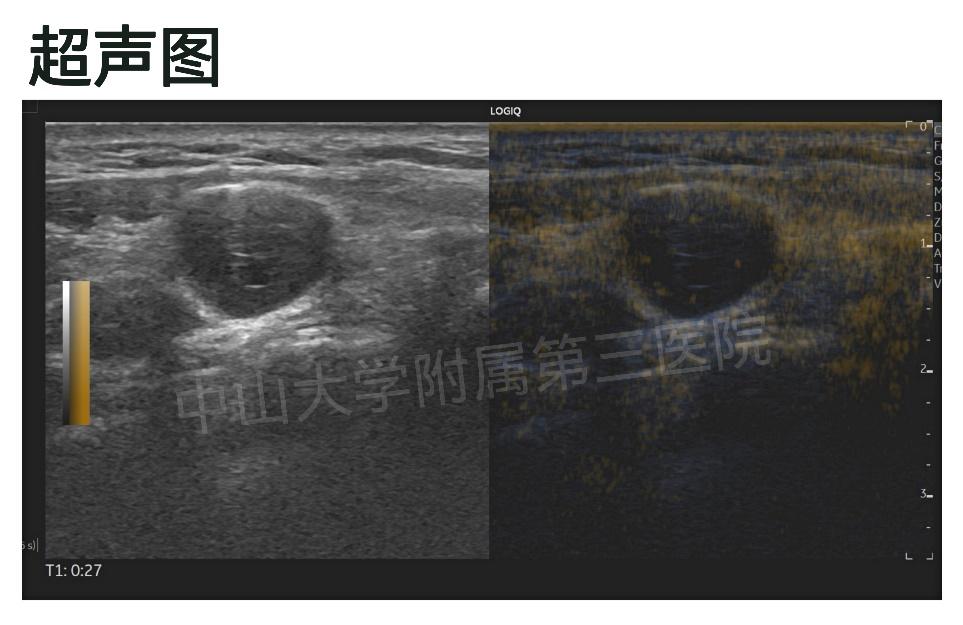

今年一月初,罗阿姨来找到我,一进来就很紧张地问我能不能做消融。我了解罗阿姨的病情后,给她详细地做了彩超加超声造影检查,超声提示右侧颈部II区见一个低回声团,约一个多公分大,造影状态下低回声团实性部分有灌注。

我跟罗阿姨解释说:考虑是神经来源肿瘤性病变与淋巴结转移Ca鉴别。在做消融之前,我们要先诊断清楚它是什么?由于彩超不能确诊,我建议罗阿姨先做活检。如果真是淋巴结转移,她这种情况可以做消融治疗,技术上不是问题。罗阿姨听我这么一说,心里刚松的一口气又提了上来,表示说:任教授,那就做活检吧,我想尽快处理了。自从发现这个小包块后,天天想着它,睡也睡不好。

验血排除罗阿姨是易出血体质后,我们给罗阿姨做了超声引导下颈部淋巴结穿刺活检。最后,病理结果提示是神经鞘瘤,不是淋巴结转移。神经鞘瘤是神经系统肿瘤中最常见的肿瘤,大多都是良性肿瘤,极少是恶性肿瘤,预后也较好,不用做消融治疗。罗阿姨这颗悬着的心才总算是放下了。